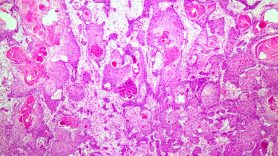

They all tend to look similar under a microscope. That’s how they get classified. But they’re further sub-categorized by where they start. You can often see the differences at the molecular level.